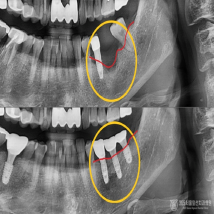

자연치아는 최대한 보존하고 빠른 회복을 위한

최소침습 임플란트

풍부한 임상경험을 토대로 잇몸뼈를 절개하지 않고

빠르고 정확하게 임플란트를 식립하여 붓기와 통증을 최소화합니다.